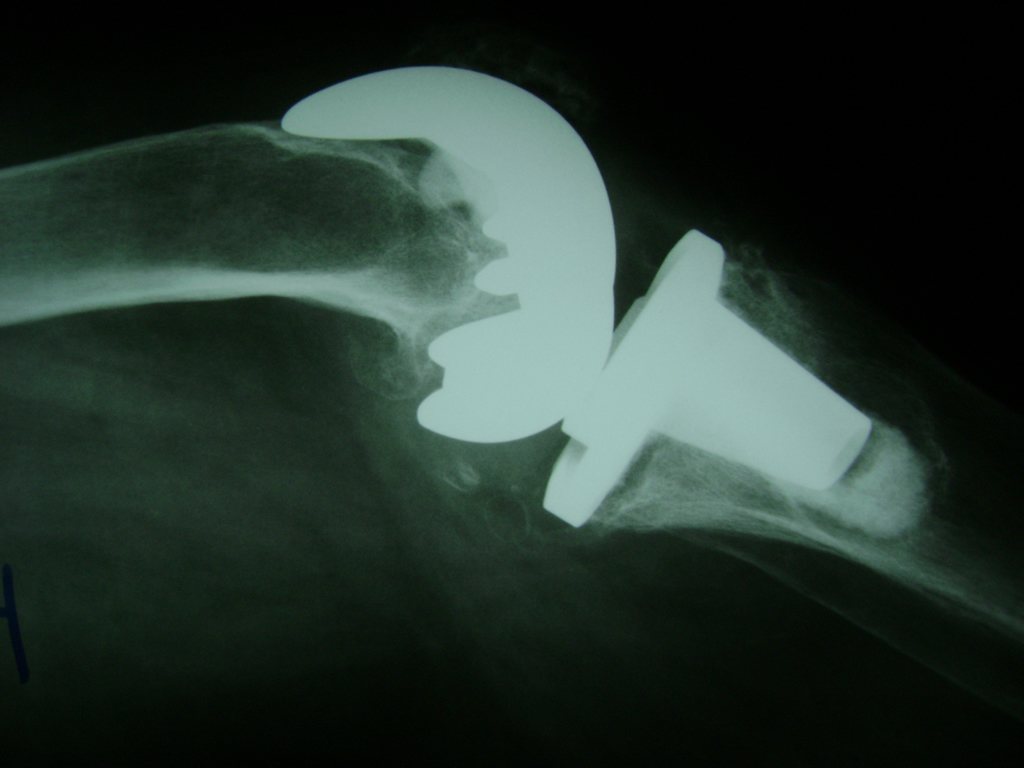

Cirugías de Húmero - Rodilla